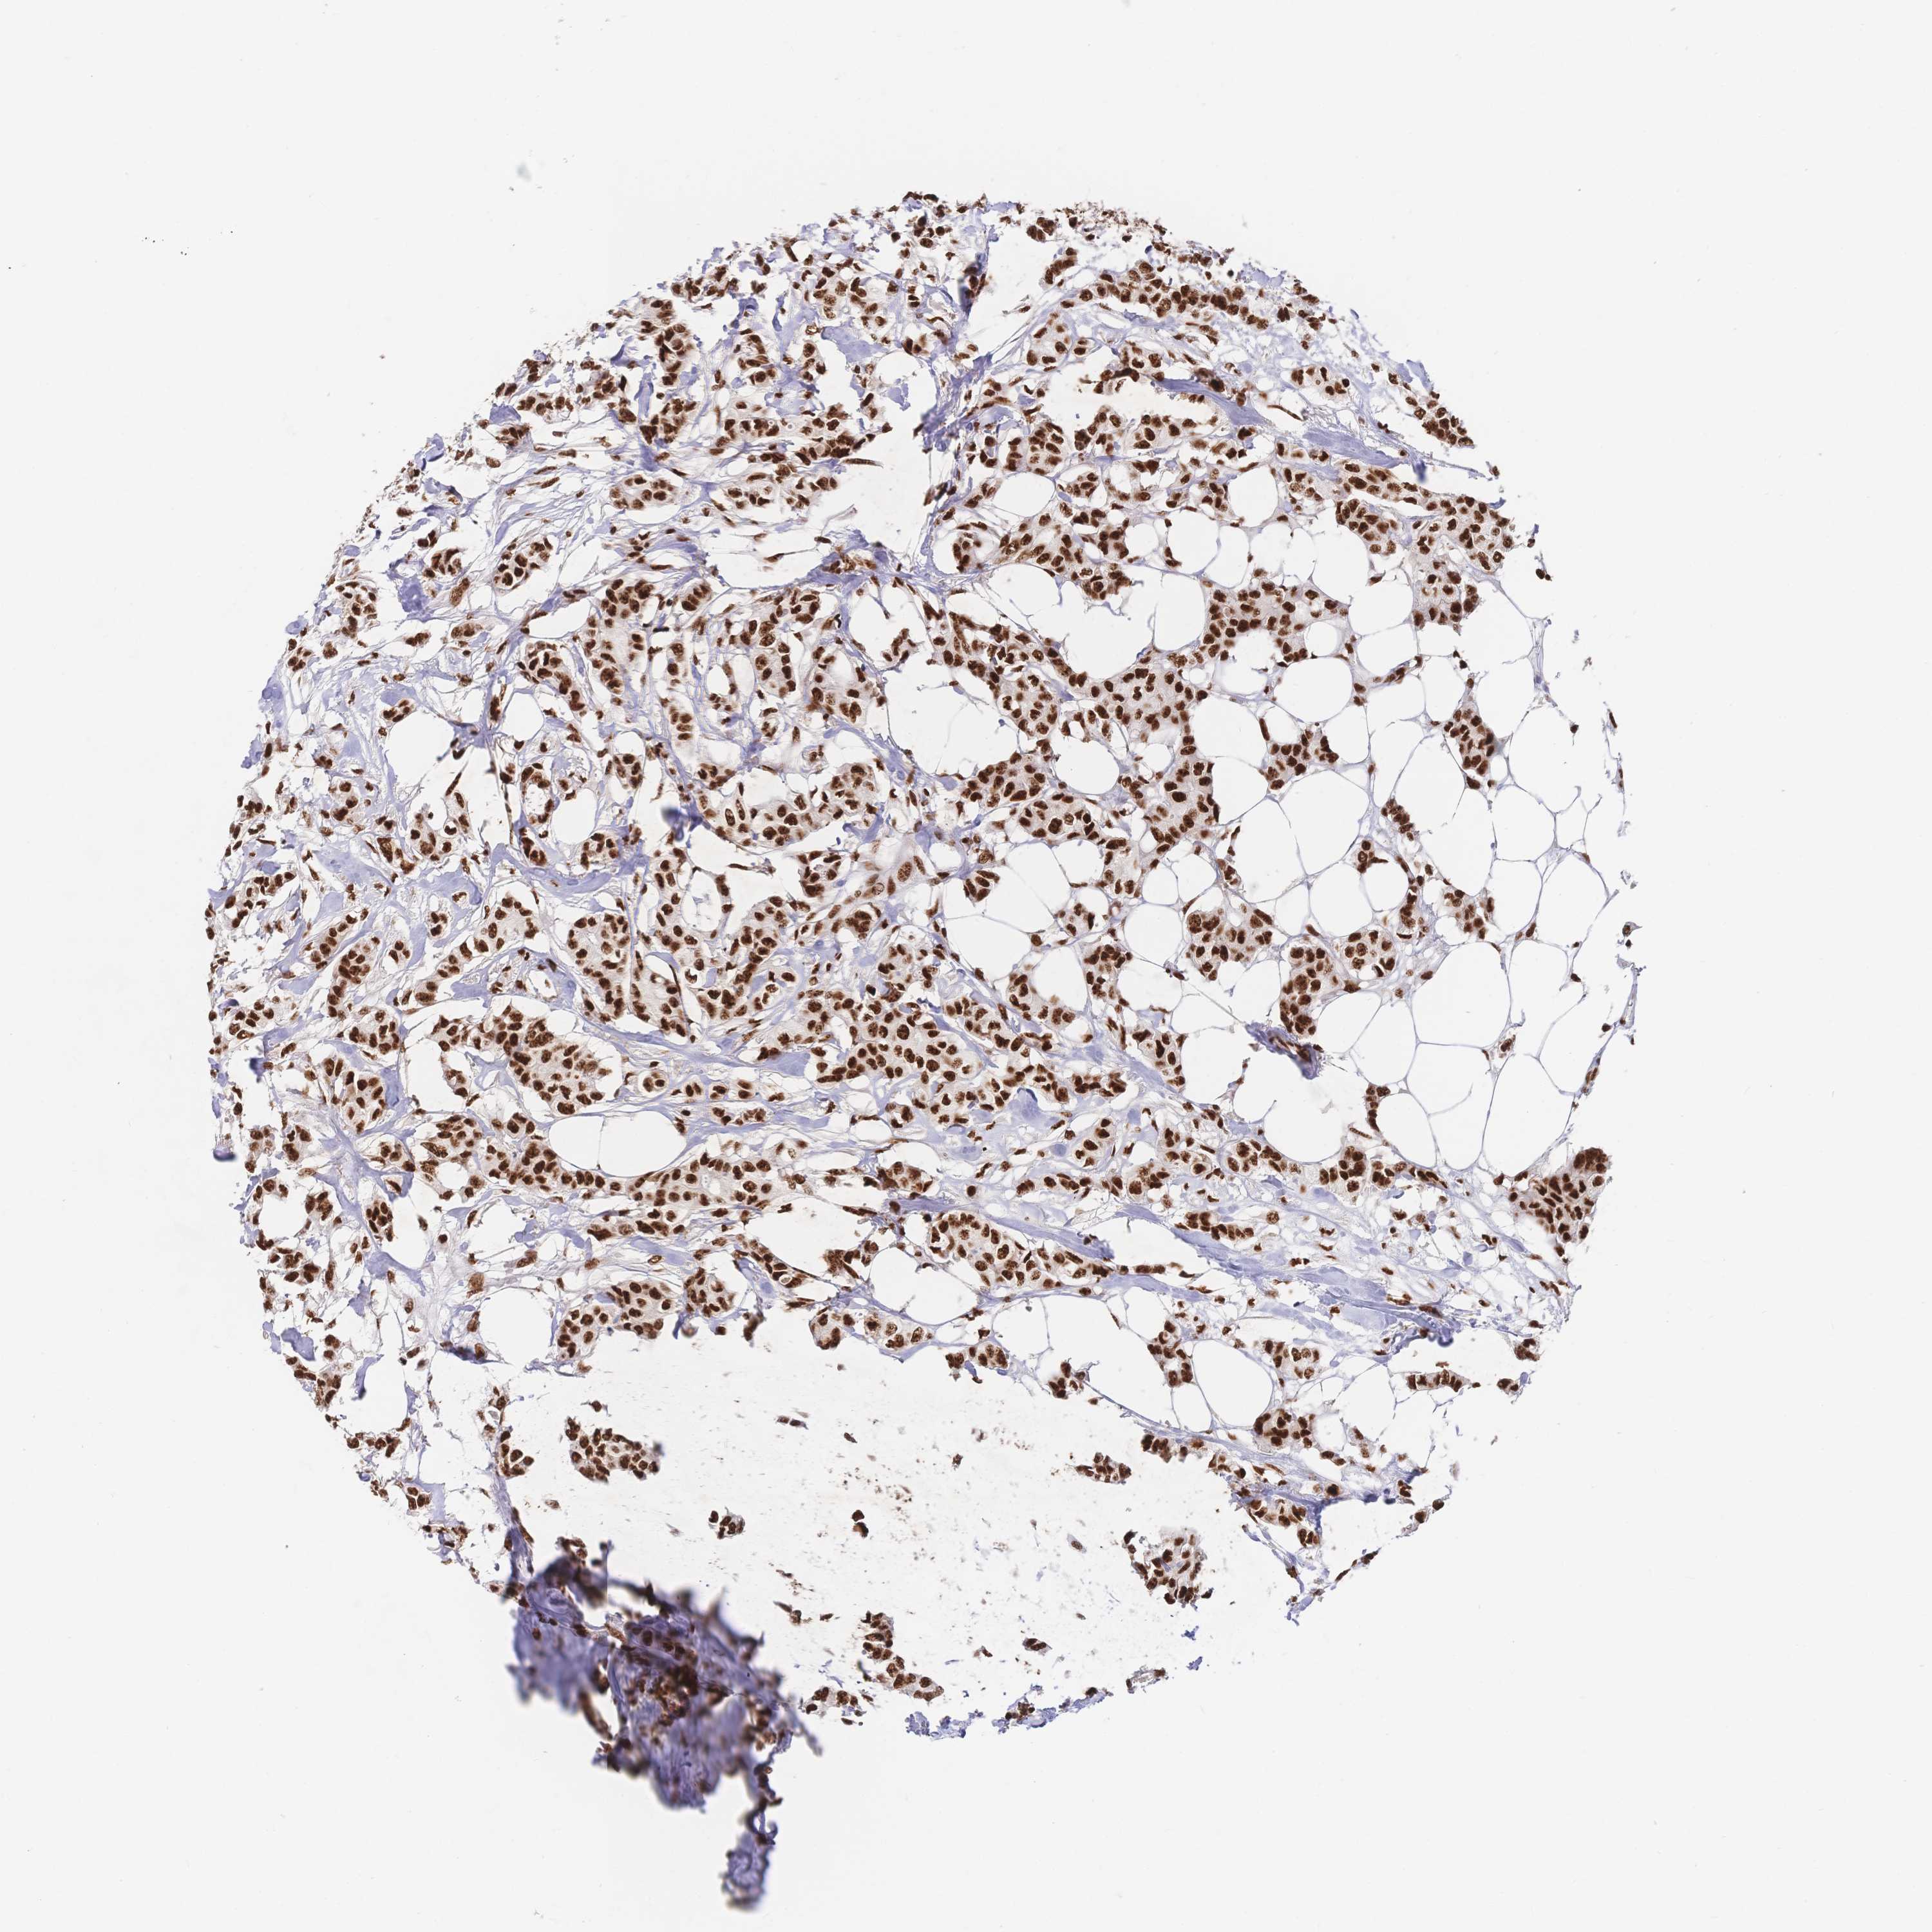

BRCA TCGA BRCA VALIDATION PROTEIN EXPRESSION